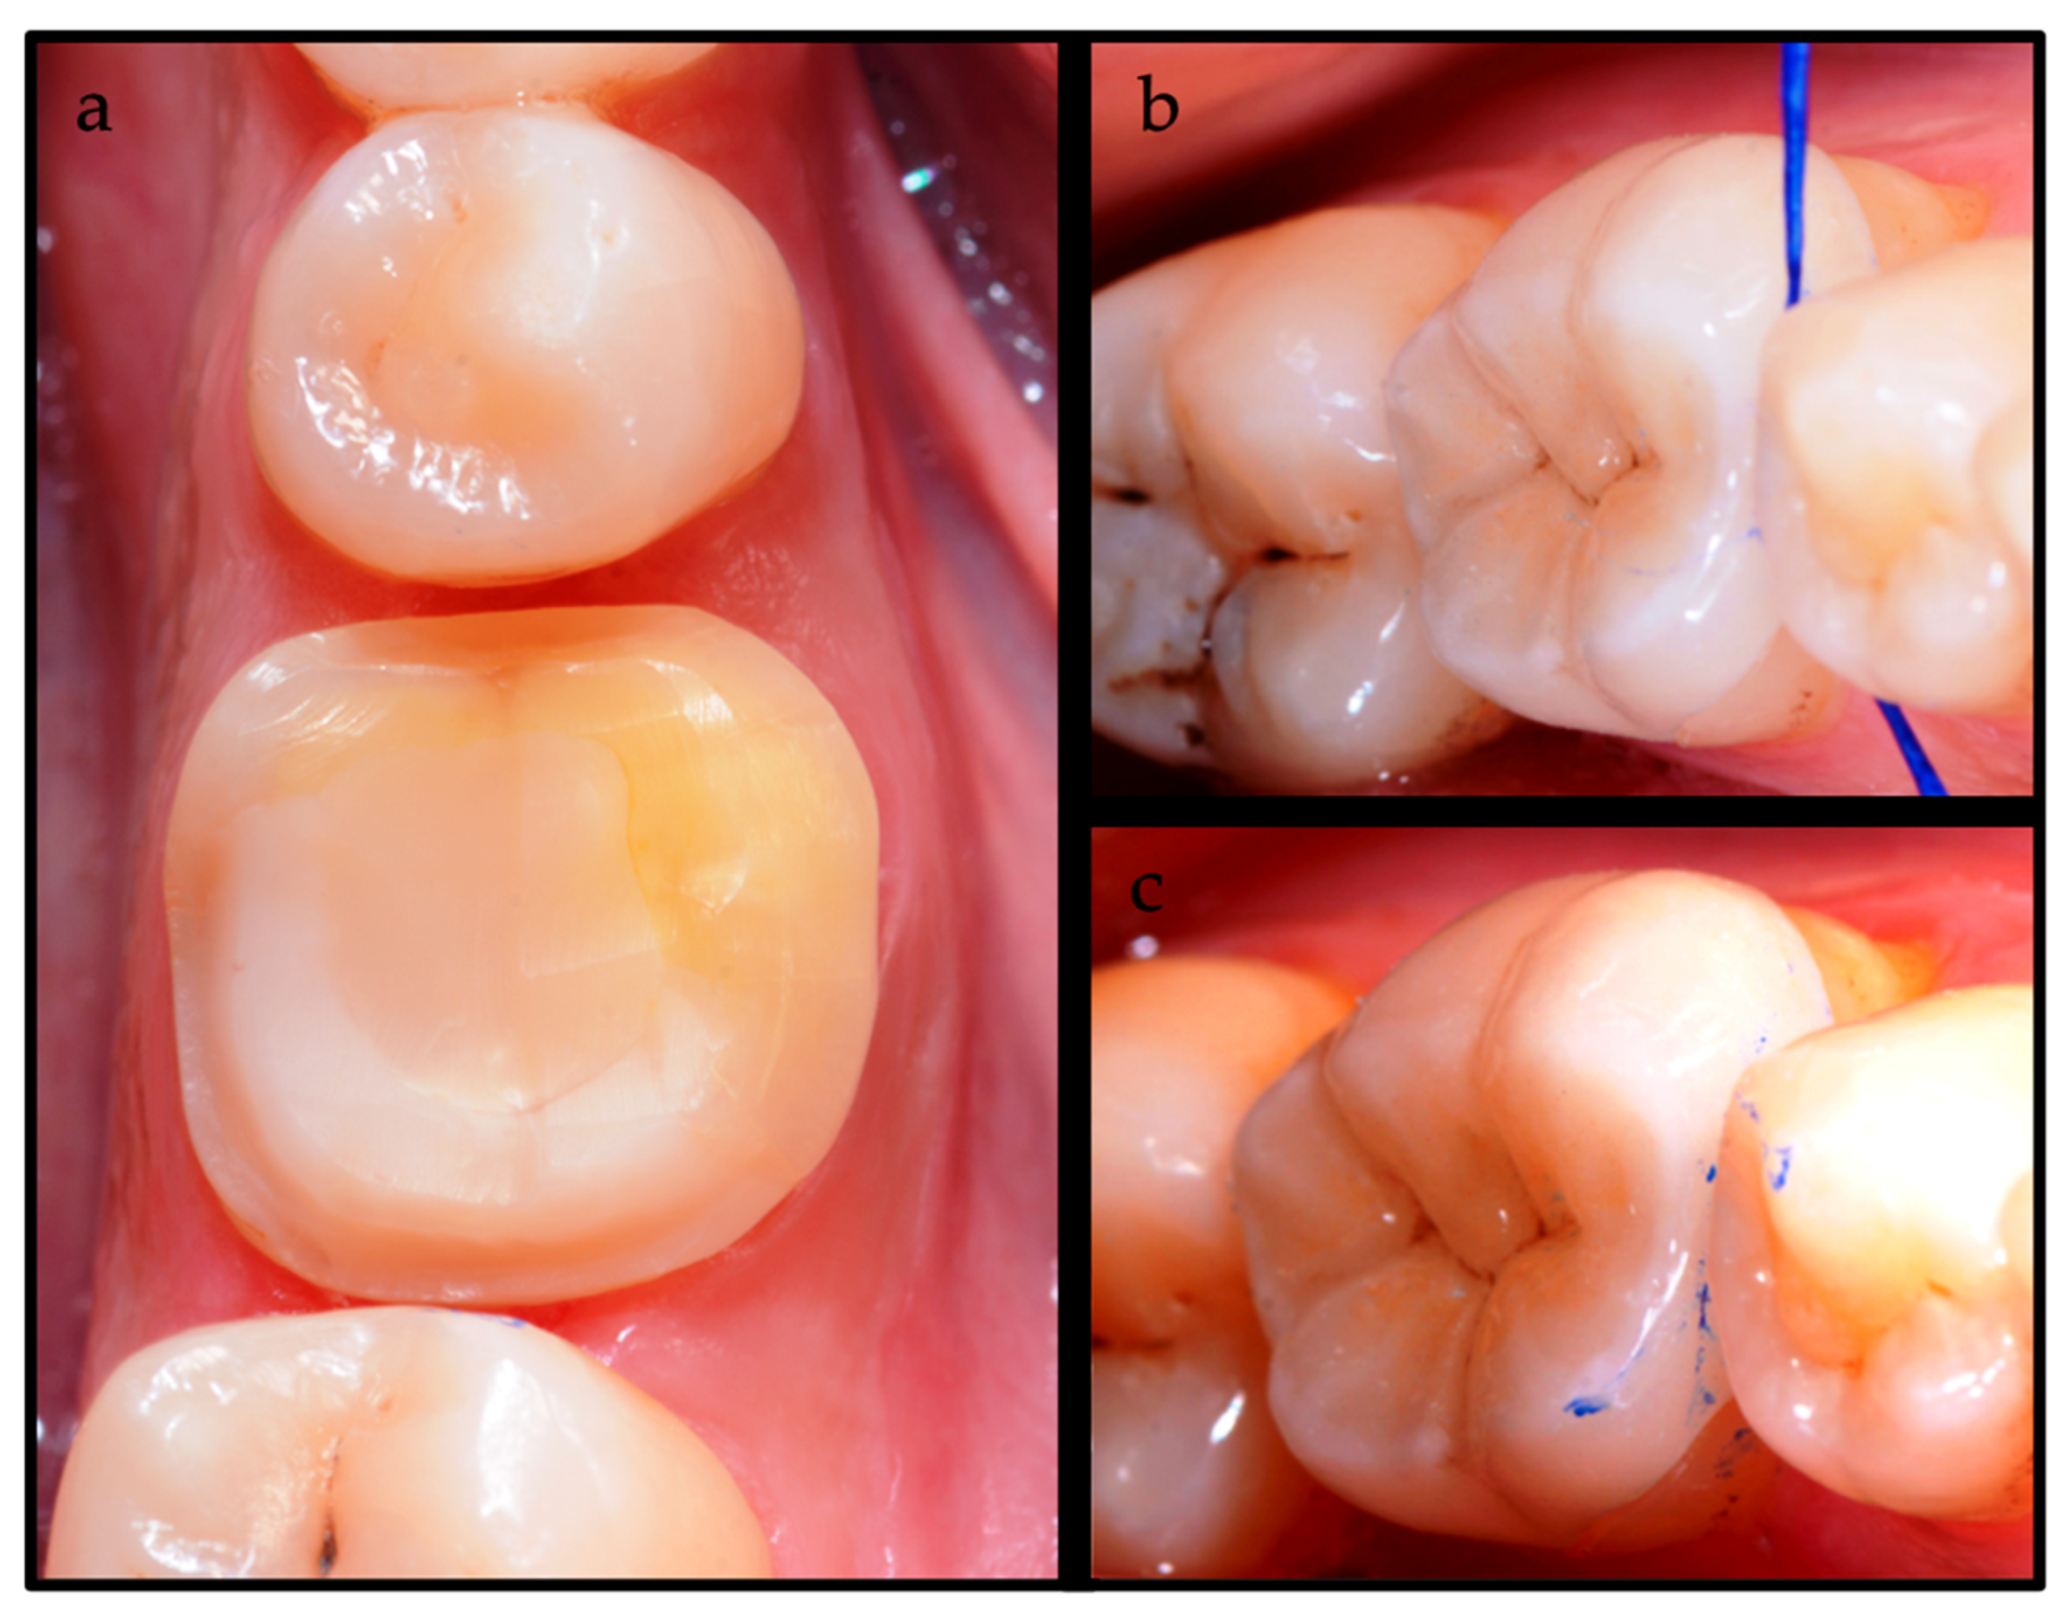

2. Case Report